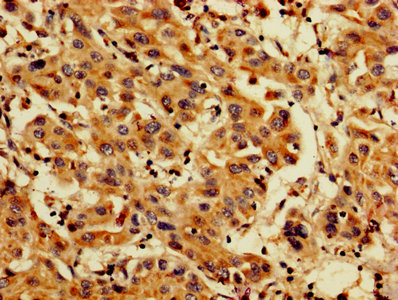

IHC image of CSB-PA04874A0Rb diluted at 1:200 and staining in paraffin-embedded human lung cancer performed on a Leica BondTM system. After dewaxing and hydration, antigen retrieval was mediated by high pressure in a citrate buffer (pH 6.0). Section was blocked with 10% normal goat serum 30min at RT. Then primary antibody (1% BSA) was incubated at 4°C overnight. The primary is detected by a biotinylated secondary antibody and visualized using an HRP conjugated SP system.